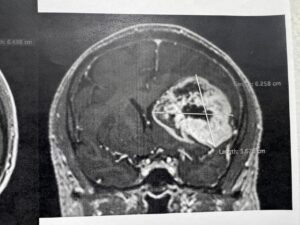

Para determinar la realización de este procedimiento y conocer el origen de los síntomas, explicó, el equipo médico del Instituto le realizó al derechohabiente estudios de tomografía y resonancia magnética.

“Se realizó tomografía de cráneo y, ante los hallazgos, se le practicó una resonancia magnética; posteriormente, se le detectó un tumor de características malignas en la región frontal premotora izquierda”.